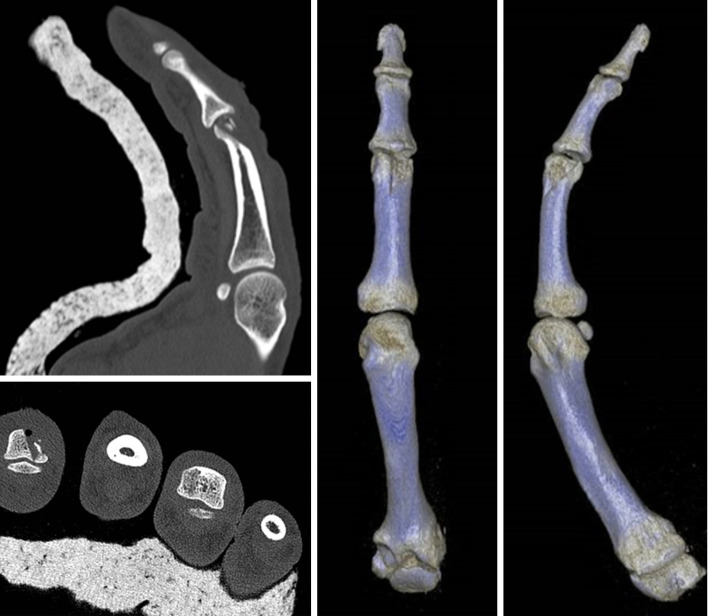

Case description: This case report highlights the successful treatment of a severe PIP joint fracture-dislocation in a 49-year-old male carpenter who sustained a traumatic laceration to the right index finger. The injury's complexity led to the pioneering use of an osteochondral autograft from the patient's second toe proximal phalanx, marking a novel approach in autologous tissue utilization for joint reconstruction. This method effectively achieved fracture resolution and joint stabilization. A comprehensive literature search was conducted up to May 2024 across multiple databases, including PubMed, Embase, Cochrane Library, Scopus, and Web of Science. The search strategy employed a combination of Medical Subject Headings (MeSH) terms and keywords related to PIP joint fracture-dislocations and osteochondral autografts. Inclusion criteria were articles in English involving human subjects, focusing on osteochondral autografts for PIP joint fracture-dislocations. Exclusion criteria included studies involving animals or cadaveric models and those not focused on osteochondral grafts. Postoperative assessments of the patient revealed successful graft integration and notable recovery in finger mobility, alongside positive functional hand outcomes as confirmed by patient-reported measures.

Conclusions: The significant enhancements in structural and functional aspects highlight the potential of this technique. Despite its sparse representation in the literature, the favourable outcomes of this case strongly support further exploration of using second toe proximal phalanx osteochondral autografts. This report underscores the need for extensive, prospective research to comprehensively ascertain the method's effectiveness and safety in addressing intricate PIP joint fracture dislocations.